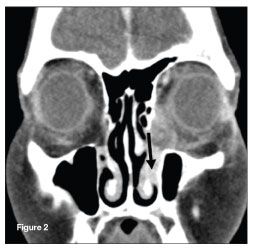

A maxillofacial CT scan with contrast showed left preseptal soft tissue swelling with an opacified left nasolacrimal duct (Figure 2; arrow indicates opacified nasolacrimal duct).